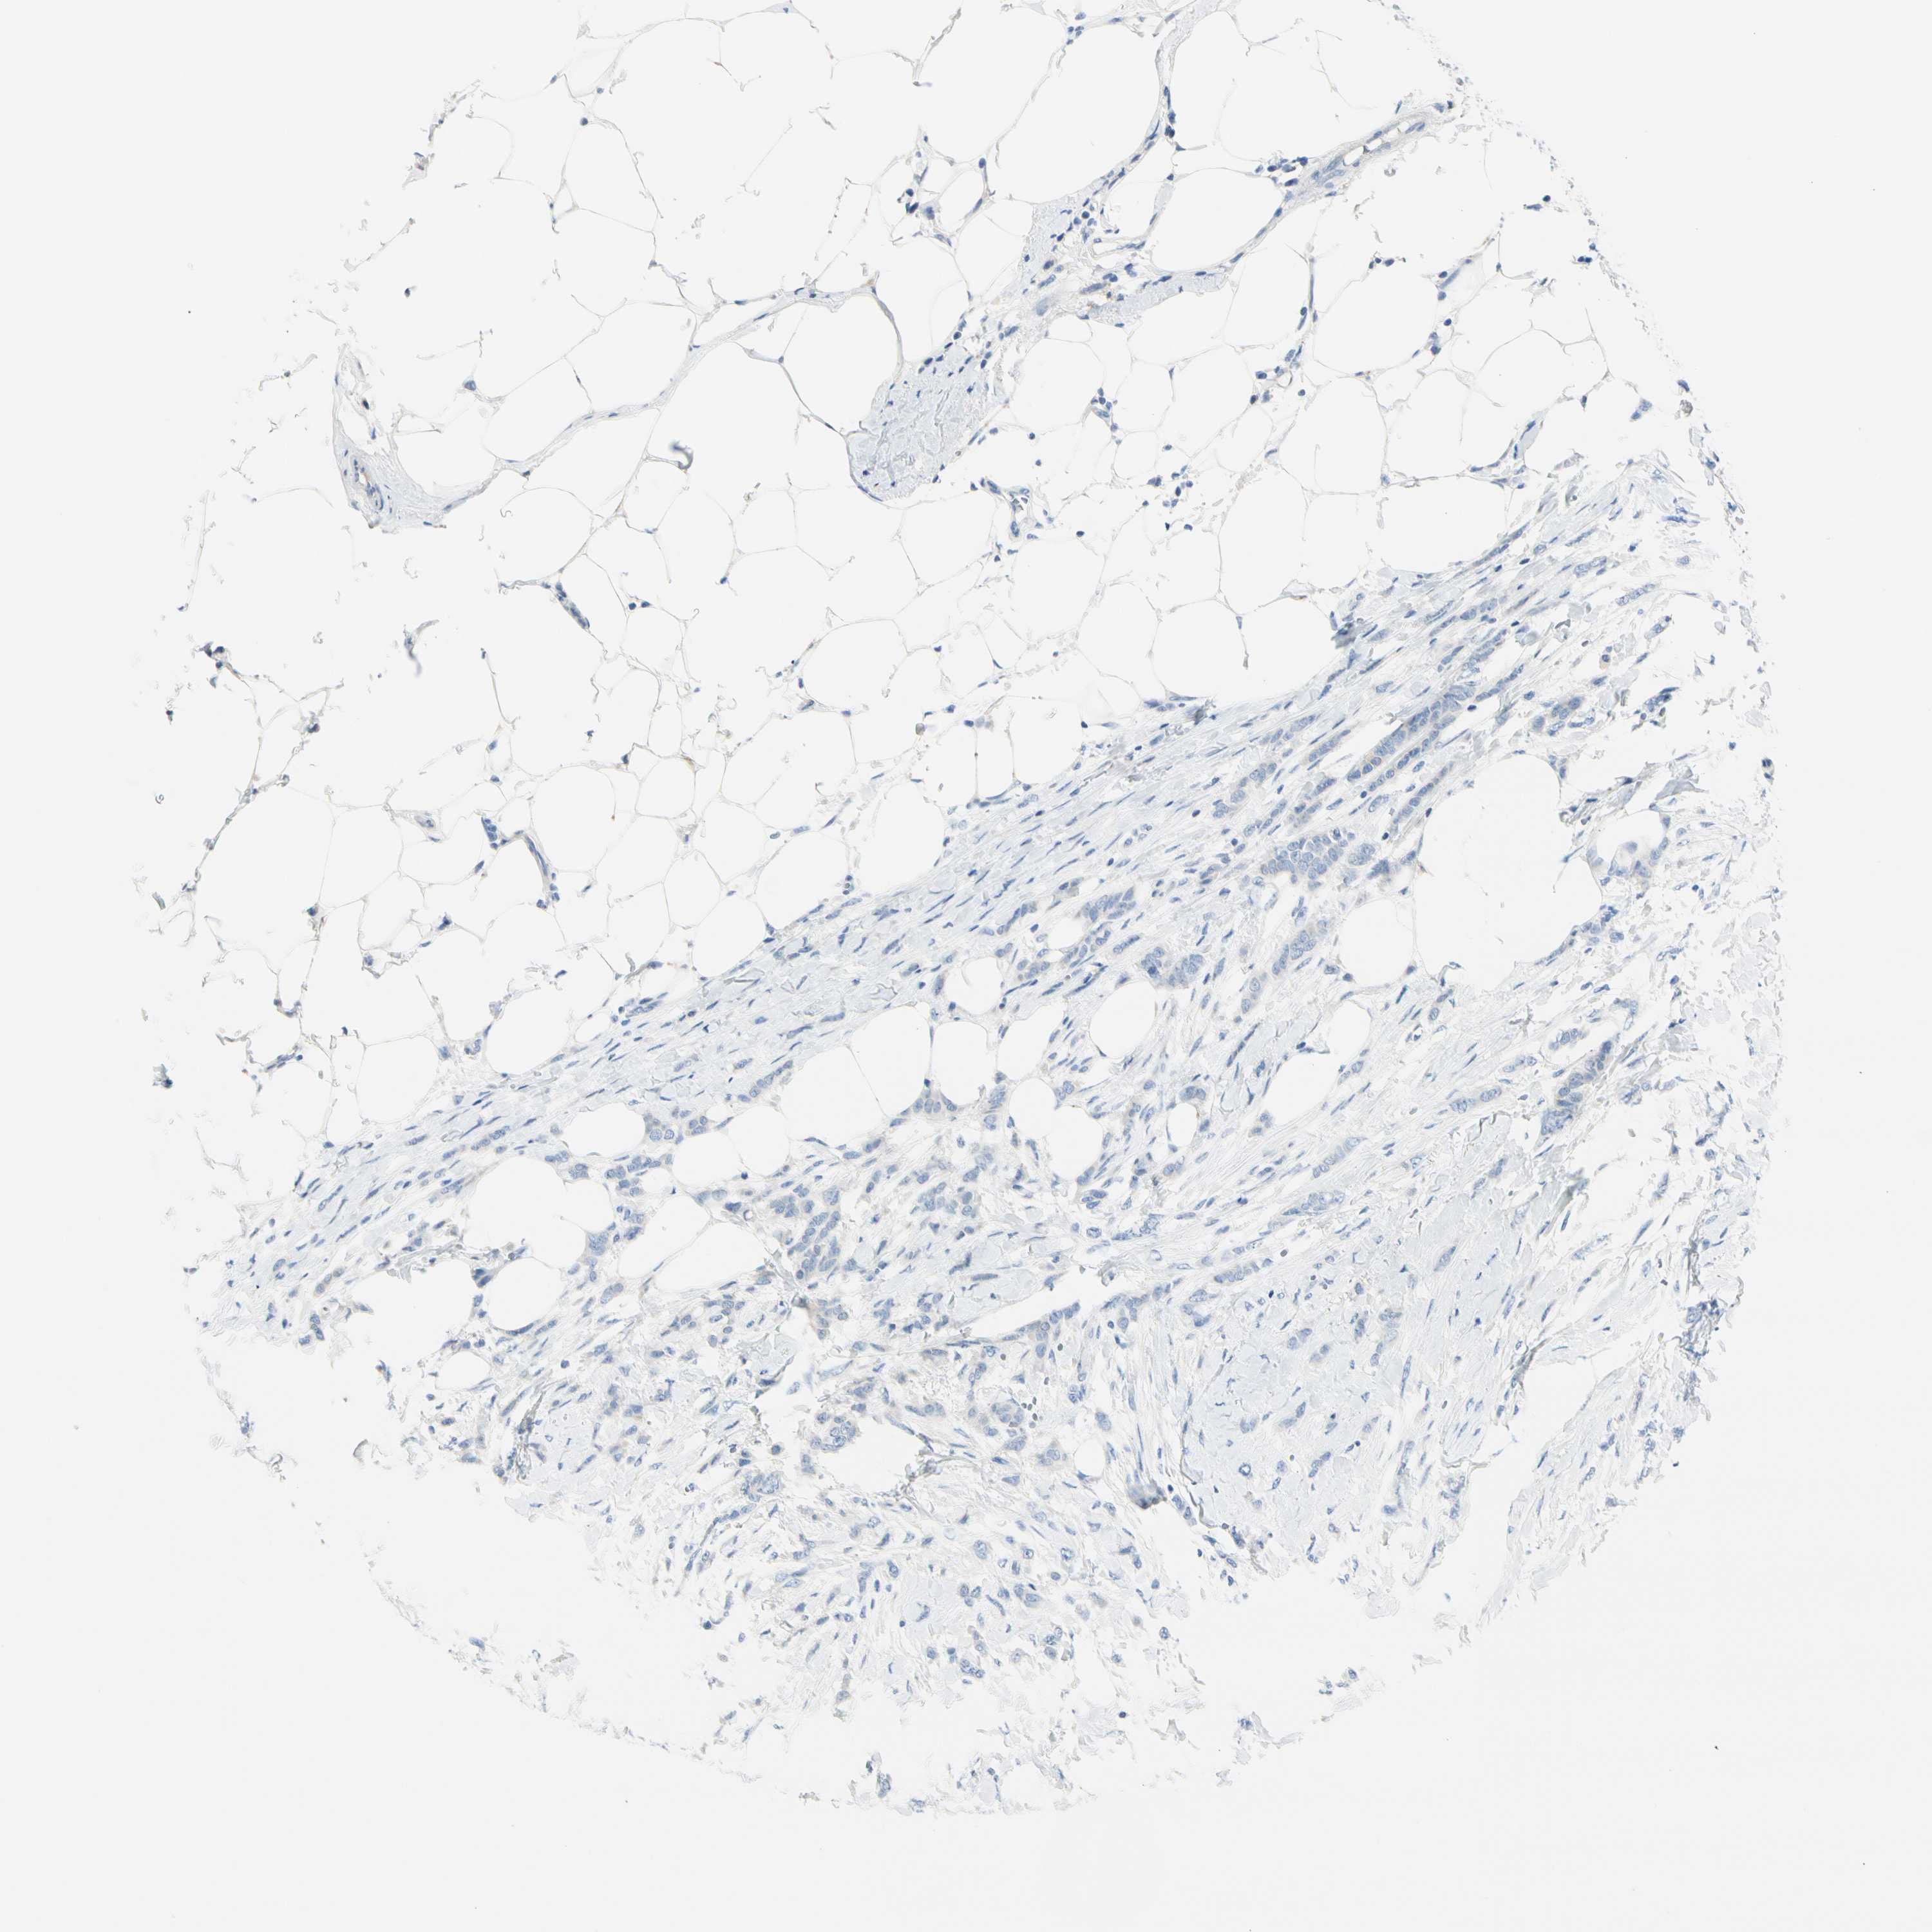

CANCER BREAST CANCER Show tissue menu

BRCA TCGA BRCA VALIDATION PROTEIN EXPRESSION

Breast cancer

Human cancer